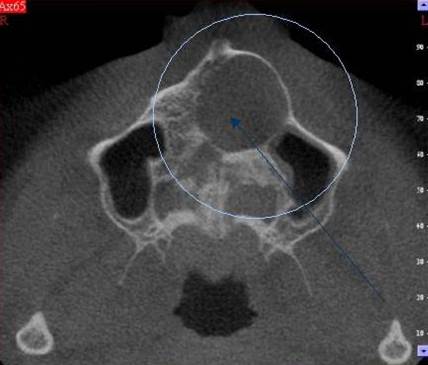

Cysty, granulomy

Vznikají při chronických (dlouhodobých) zánětech tkání kolem hrotu zubu - granulomy (tzv. váčky).

Mohou dosahovat v průměru od několika mm až po několik cm. Pak již hovoříme o cystách. Léčba spočívá v odstranění tohoto ložiska spolu s hrotem zubního kořene tzv. resekce kořenového hrotu.

Vyšetření pomocí tohoto přístroje používáme i ve stomatochirurgii (zlomeniny čelistí, zuby moudrosti, cysty, onemocnění čelistního kloubu), ortodoncii (retinované zuby, nadpočetné zuby), parodontologii atd.